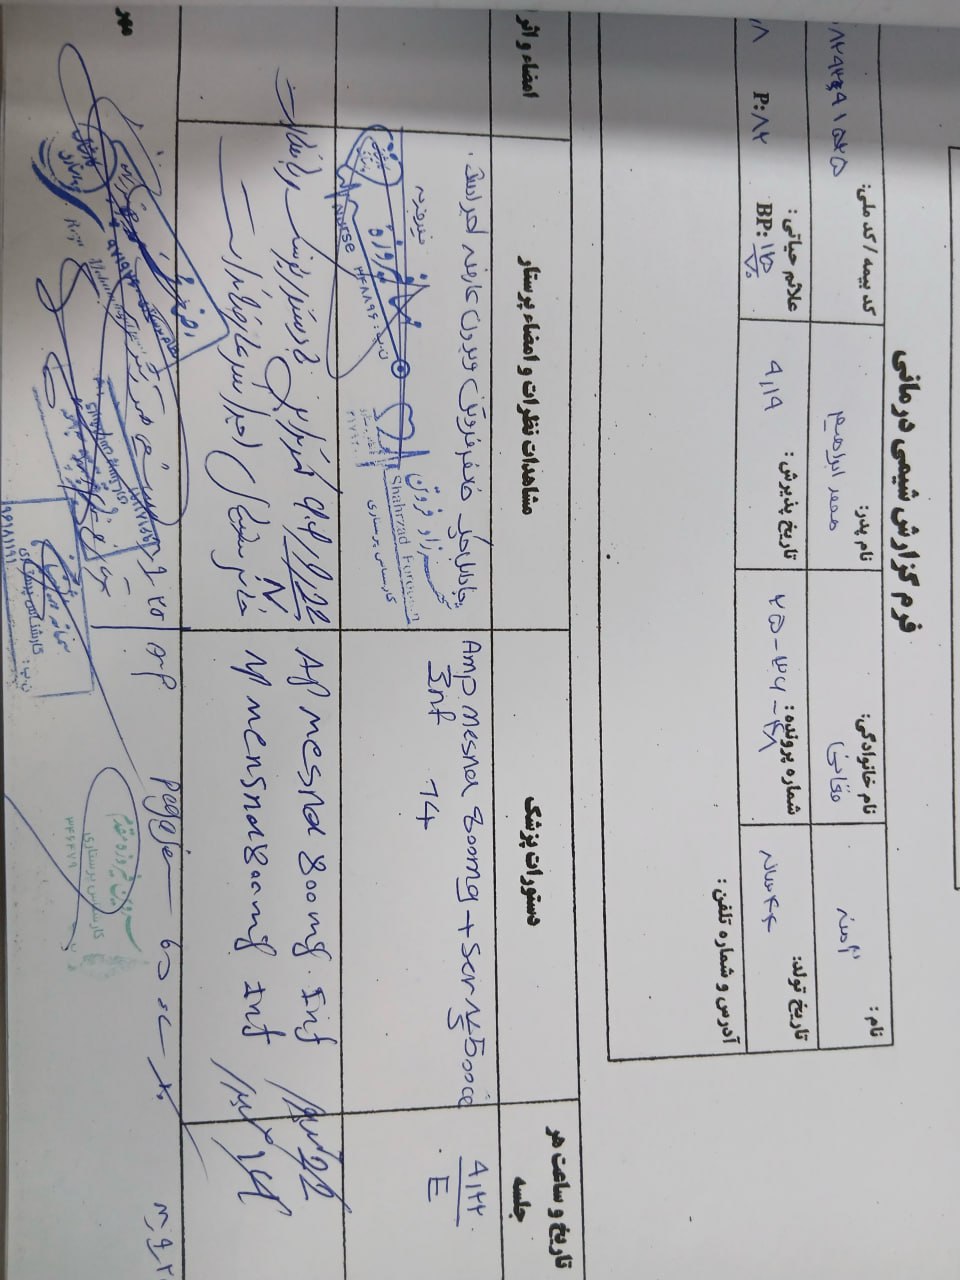

به ترتیب؛ روز ها: ۱۹ آبان, ۲۸ آذر, ۲۹ آذر, ۳۰ آذر

به ترتیب؛ روز ها: ۱۹ آبان, ۲۸ آذر, ۲۹ آذر, ۳۰ آذر

به ترتیب؛ روز ها: ۲۸ آذر, ۲۹ آذر, ۳۰ آذر, ۱ دی

۱ دی